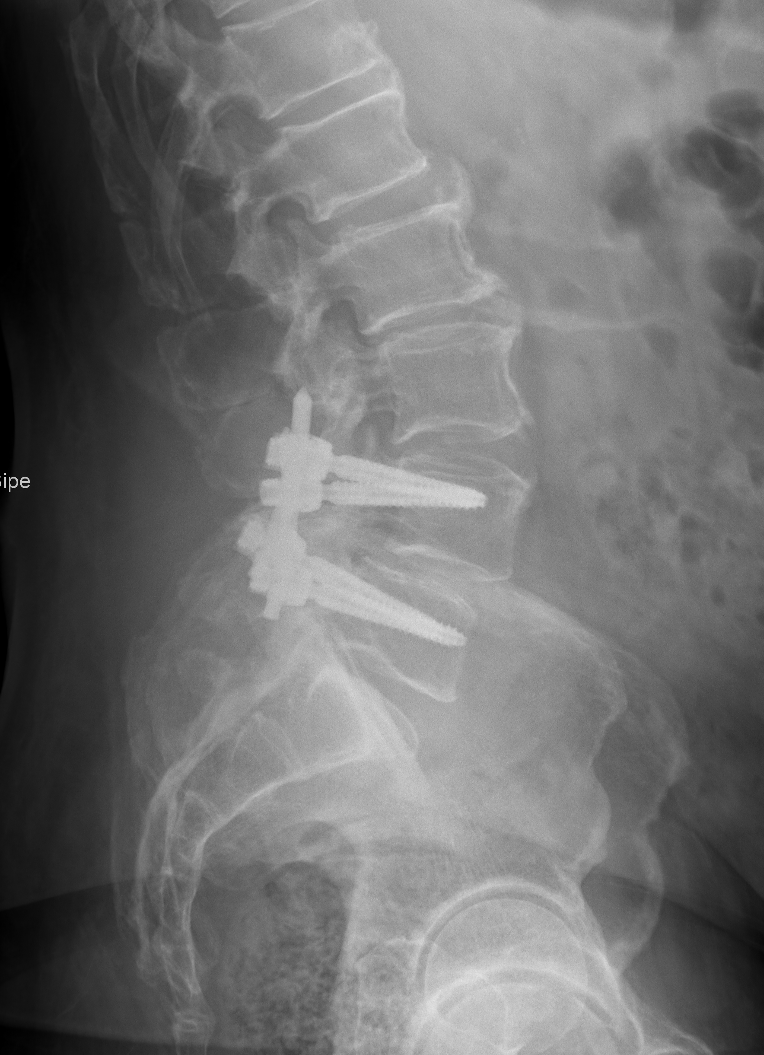

Les imatges postoperatòries mostren un posicionament perfecte dels implants! ✅

💪Postoperative images show perfect implant positioning! ✅